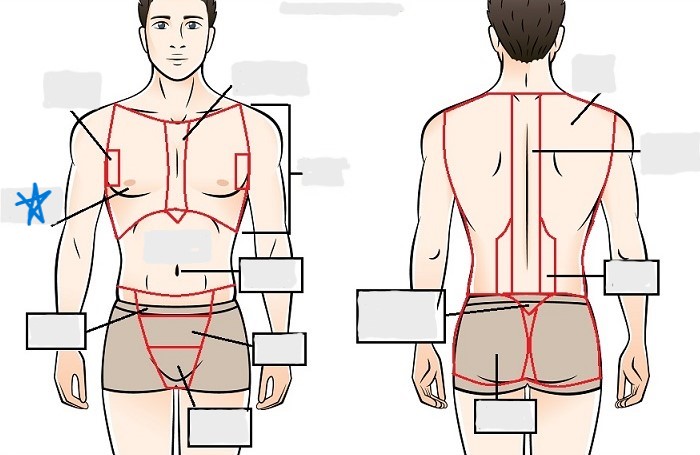

axial

cephalic

occipital

frontal

otic

orbital

nasal

oral

mental

cervical

dorsal

scapular

vertebral

lumbar

sacral

gluteal

thoracic

sternal

mammary

axillary

abdominal

umbilical

pelvic

inguinal

pubic

perineal

appendicular

acromial

brachial

antecubital

olecranal

antebrachial

carpal

manus

coxal

femoral

patellar

popliteal

crural

sural

peroneal

calcaneal

plantar